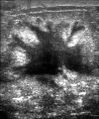

يتضمن الفحص السريري أو الذاتي للثدي تحسس الثدي للوقوف على وجود كتل أو أي تشوهات أخرى. يتم إجراء فحوصات الثدي السريرية من قبل مقدمي الرعاية الصحية، بينما تُجرى فحوصات الثدي الذاتية من قبل الشخص نفسه.[109] لا تدعم الأدلة فعالية أي من نوعي فحوصات الثدي، لأنه بحلول الوقت الذي يصبح فيه الورم كبيرًا بما يكفي ليتم اكتشافه، من المحتمل أن ينمو لعدة سنوات وبالتالي يصبح كبيرًا بما يكفي ليتم لاكتشافه بدون فحص.[110][111] يستخدم فحص التصوير الإشعاعي لسرطان الثدي بالأشعة السينية لفحص الثدي بحثًا عن أي كتل. أثناء الفحص، يتم ضغط الثدي ويلتقط الفني صورًا من زوايا متعددة. يلتقط التصوير الشعاعي للثدي العام صورًا للثدي بأكمله، بينما يركز تصوير الثدي الشعاعي التشخيصي على كتلة معينة أو منطقة معينة مثيرة للقلق.[112]

يمكن أن توفر طريقتا الفحص الأكثر شيوعًا، وهما الفحص البدني للثدي بواسطة مقدم الرعاية الصحية والتصوير الإشعاعي للثدي، احتمالًا تقريبيًا لوجود كتلة سرطانية، وقد تكتشف أيضًا بعض الآفات الأخرى، مثل الكيسات البسيطة.[122] عندما تكون هذه الفحوصات غير حاسمة، يمكن لمقدم الرعاية الصحية أخذ عينة من السائل الموجود في الكتلة لتحليلها مجهريًا (إجراء يُعرف باسم الخزعة بالإبرة) للمساعدة في تحديد التشخيص. يمكن إجراء الخزعة بالإبرة في عيادة أو مكتب مقدم الرعاية الصحية. يمكن استخدام مخدر موضعي لتخدير أنسجة الثدي لمنع الألم أثناء العملية، ولكن قد لا يكون ضروريًا إذا لم يكن الورم تحت الجلد. إن اكتشاف وجود سائل واضح يجعل الكتلة غير سرطانية إلى حد كبير، ولكن قد يتم إرسال السائل الدموي للفحص تحت المجهر بحثًا عن الخلايا السرطانية. يمكن استخدام الفحص البدني للثدي، والتصوير الشعاعي للثدي، والخزعة بالإبرة معاً لتشخيص سرطان الثدي بدرجة جيدة من الدقة.

تشمل الخيارات الأخرى لأخذ الخزعة الخزعة الأساسية أو vacuum-assisted breast biopsy،[123] وهي الإجراءات التي يتم فيها إزالة جزء من كتلة الثدي؛ أو الخزعة الاستئصالية، حيث يتم إزالة الورم بأكمله. غالبًا ما تكون نتائج الفحص البدني من قبل مقدم الرعاية الصحية والتصوير الشعاعي للثدي والاختبارات الإضافية التي يمكن إجراؤها في ظروف خاصة (مثل التصوير بواسطة الموجات فوق الصوتية أو التصوير بالرنين المغناطيسي) كافية لتبرير الخزعة الاستئصالية كطريقة تشخيصية وعلاجية أولية.[124][بحاجة لمصدر غير رئيسي]